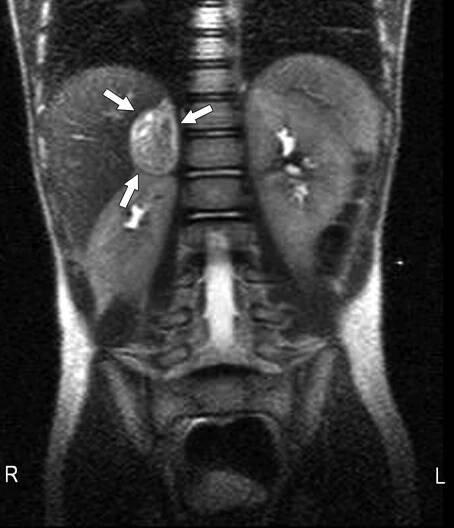

Feochromocytom je nádor, který se nachází v dřeni nadledviny (tj. ve středové části žlázy, která shora přiléhá k ledvině) a způsobuje nadměrnou tvorbu adrenalinu. Feochromocytomy jsou obvykle nezhoubné neboli benigní (tzn. nejedná se o rakovinu), ale mohou způsobovat vysoký krevní tlak, bolest hlavy,…

Feochromocytom je zajímavý typ nádoru nadledvin, který vychází z jejich dřeně. Většinou je nezhoubný (někdy však může být i zhoubný a vytvářet metastázy), ale přesto může ohrožovat nemocného na životě.

Feochromocytomy jsou vzácné neuroendokrinní nádory s velmi proměnlivými klinickými projevy, pro nějž jsou typické záchvatovité obtíže – bolesti hlavy, pocení, palpitace a hypertenze.